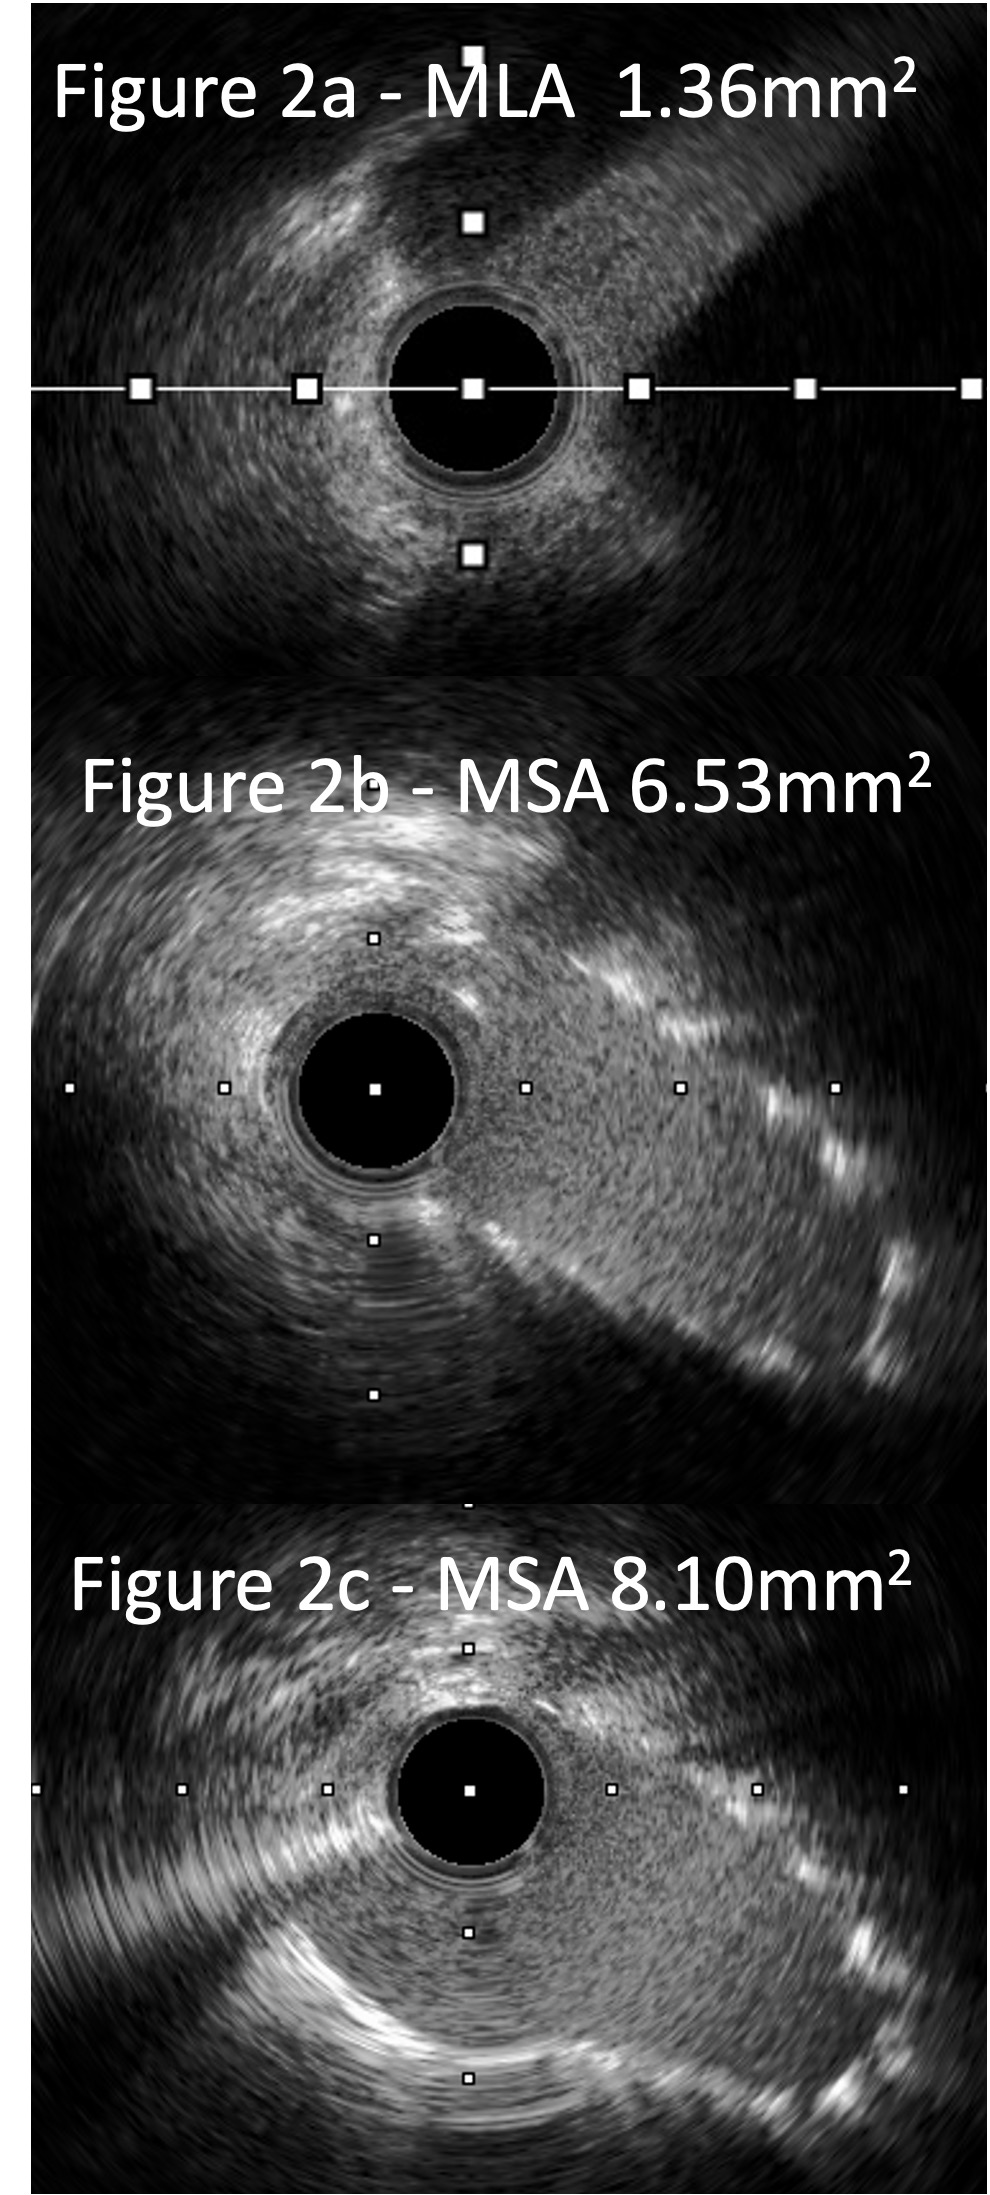

Intravascular ultrasound (IVUS) demonstrated severe ostial disease with a ¡°slit-like¡± appearance and a minimal luminal area (MLA) of 1.36mm2 (Figure 2a) with dynamic compression of the proximal RCA. The fibrotic RCA ostium was treated with a 3.5mm Wolverine Cutting Balloon. Real-Time IVUS ostial stenting was performed with a 3.5 x 16mm Megatron deployed. Post stent IVUS showed persistent dynamic compression at the ostium with a minimal stent area (MSA) of 6.53mm2 (Figure 2b). A 2nd 3.5 x 12mm Megatron was deployed over the 1st stent and post dilated with a 4.0 NC balloon to enhance its radial strength. Final IVUS showed minimal stent compression with an MSA of 8.1mm2 (Figure 2c). Final angiogram showed TIMI 3 flow (Figure 1b).